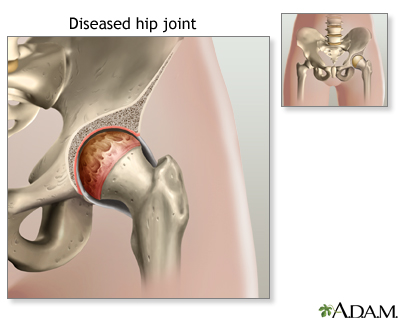

The most common reason to have this surgery is to relieve arthritis. Severe arthritis pain can limit your activities.

Most of the time, hip joint replacement is done in people age 60 and older. Many people who have this surgery are younger. Younger people who have a hip replaced may put extra stress on the artificial hip. That extra stress can cause it to wear out earlier than in older people. Part or all of the joint may need to be replaced again if that happens.

Diseased hip - illustration

Diseased hip

illustration